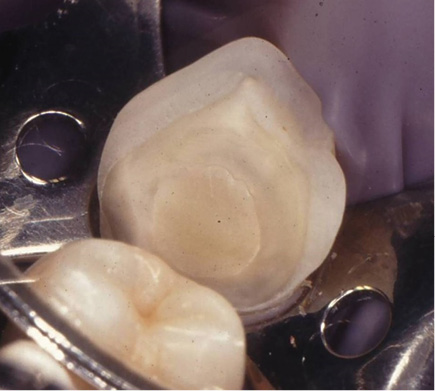

Fig.

2b EC in #34 after 19 years (IPS-Empress, Ivoclar, Vivadent,

Liechtenstein). The glass-ionomer in gingival had a survival time of 23

years and needed to be repaired